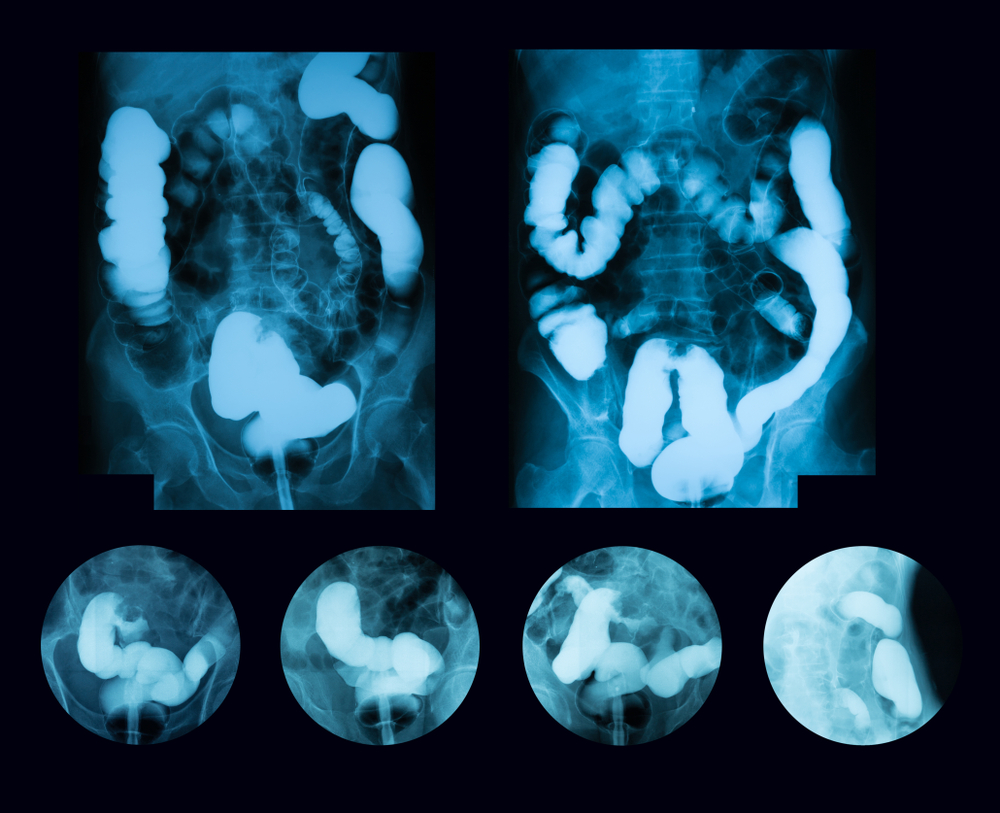

Рентгеноконтрастные Исследования Кишечника: Визуализация и Методики

Раздел: Иллюстрированный журнал